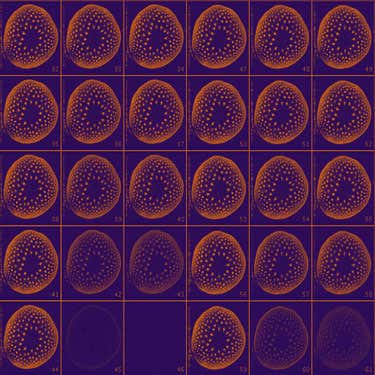

3D mouse atlas

Researchers at University College London are using the power of micro-magnetic resonance imaging to detect structural abnormalities and their genetic cause. The MRI can pick up minute changes in the brain or heart like a hair-width hole in an embryo’s heart. Peter Scambler and colleagues are using the technique to study the genes responsible for this heart defect in humans. The centre figure is a composite of dozens of mouse embryos, which serves as an atlas to calculate the effects of a gene on anatomy. The higher magnetic field of the scanner allows the device to probe fine detail, capturing images with less than 40 micron resolution.

(Image: UCL CABI)